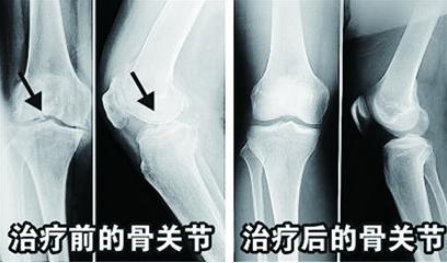

(治疗前后的片子对比)